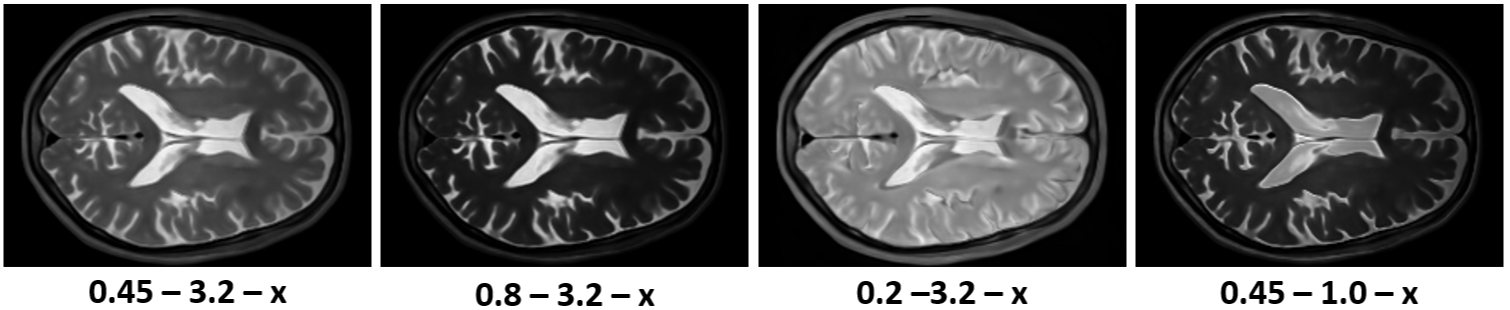

A key advantage of our physics-informed generative model over previous methods is the ability to synthesize modalities not present in the training data. Figure 3 shows how changes in the acquisition parameters affect the generated images using different signal models given a single tissue property map generated by our model. Although we can generate various novel MR contrasts, some acquisition parameter combinations can still lead to unrealistic images with bright backgrounds.

The employed signal model only considers a perfect MR scanner that does not add any noise to images. Thus, the MRI scans generated by our model do not contain any noise either Figure 5. While this might be desirable for some applications, noise is required to create realistic MRI scans. One solution could be to model the residual noise separately using another diffusion model conditioned on the noise-free MRI scan [16]. Additionally, the accuracy of the tissue property maps is limited by the number of available MR contrasts per scanning session. This issue could be addressed by introducing location-dependent priors based on the expected tissue type, such as white matter, grey matter, and cerebrospinal fluid. A more robust evaluation of the generated tissue properties would furthermore require access to real tissue property maps, which advanced quantitative MRI techniques can obtain [13].